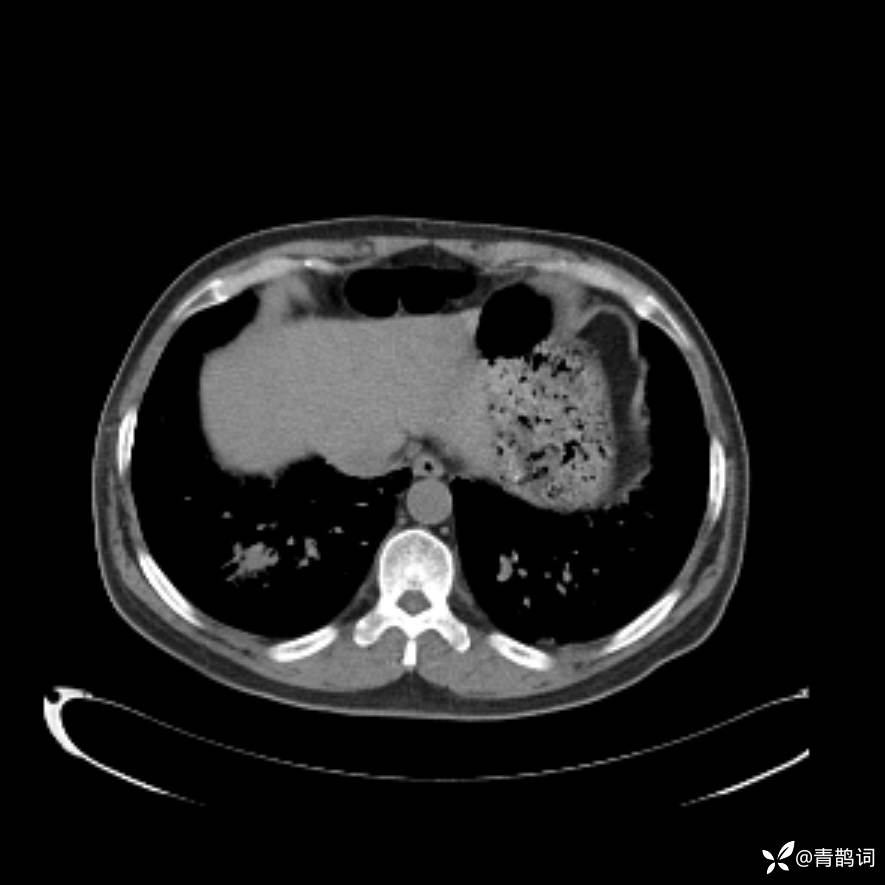

患者年龄:30岁。

患者性别:男。

简要病史:左颜面部肿胀2年,反复咳嗽咳痰,逐渐加重。

辅助检查